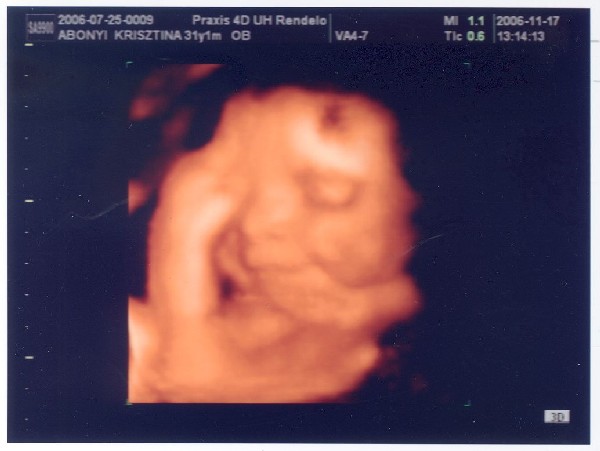

Ma vagyunk 31 hetesek, irány 4d délután!!! Hétfőn rakok fel fotót!!!

Szuper, hogy már a 31.hetet tapossátok!!! És már mindent megvettetek majdnem? Húúú, nagyon ügyik vagytok!!! :) Puszi Nektek! :D Remélem kapunk 4D-s képet Krisztina-hercegnőről :D